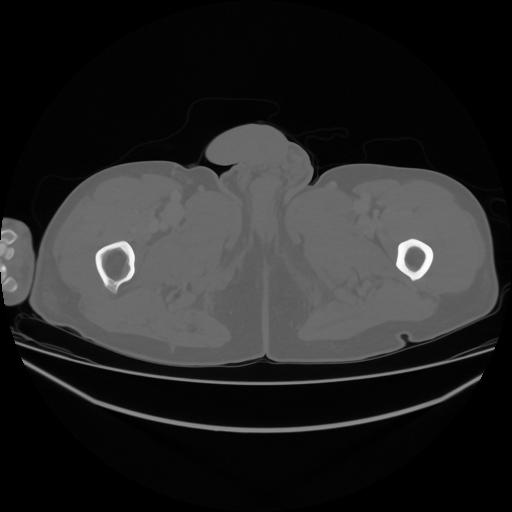

5 CUERPO,CE,Vol,1.0,CUERPO,,